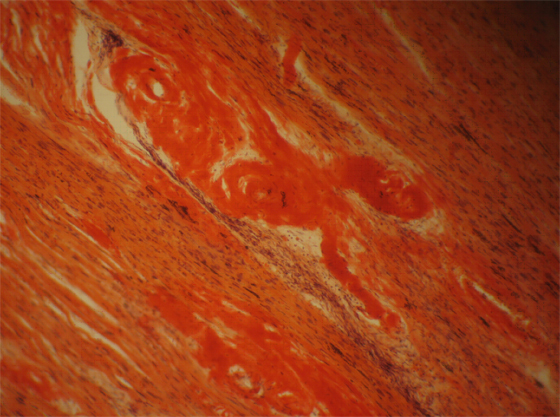

В 2 случаях в танатогенезе превалировала прогрессирующая левожелудочковая сердечная недостаточность. Макроскопически выявлена кардиомегалия, утолщение клапанов сердца. Микроскопически определялись глыбчатые отложения амилоида в эндокарде, строме миокарда, а также в стенке сосудов всех типов (рис.1). Особенно большие отложения амилоида обнаруживались в мелких артериальных и частично венозных сосудах миокарда и эпикарда. В сосудах несколько более крупного калибра отложение амилоида определялось в адвентиции и периадвентициальной ткани.

Рис. 1. Амилоидные массы в строме миокарда, конго красный, х200 |

В строме миокарда амилоидные массы вытесняют мышечную ткань сердца, приводя к атрофии кардиомиоцитов. Различные группы мышечных волокон подверглись гипертрофии. В некоторых участках обнаруживались дистрофические изменения кардиомиоцитов. Вокруг амилоидных масс выявились диффузные разрастания соединительной ткани с перифокальной умеренной лимфоплазмоцитарной инфильтрацией.